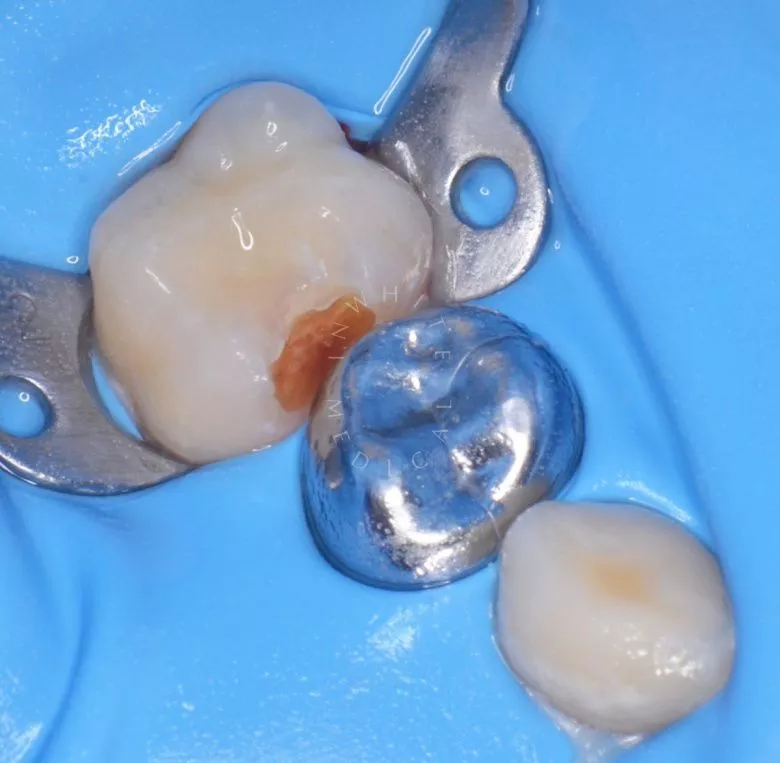

етская стоматология лечение под наркозом. Лечение под наркозом - установка коронок и профессиональная гигиена у детей - до процедуры

етская стоматология лечение под наркозом. Лечение под наркозом - установка коронок и профессиональная гигиена у детей - после процедуры